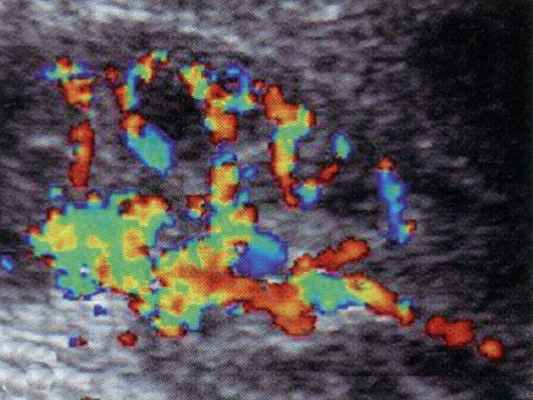

Принципиальное значение имеет оценка ренального кровотока в динамике сердечного цикла. В норме кровоток визуализируется на протяжении всего сердечного цикла, при этом обеднение его в диастолу соответствует снижению скорости кровотока при допплерографии (рис. 2а). Резистивный индекс RI составляет около 0,6. В ангиотромботической фазе гемолитико-уремического синдрома дуплексное допплеровское сканирование позволяет визуализировать кровоток только в систолическую фазу сердечного цикла. В диастолу кровоток в сосудах почки не определяется, что соответствует отсутствию антеградной диастолической составляющей ренального артериального кровотока (рис. 2б), соответственно, RI = 1,0. Реверсный диастолический артериальный кровоток в сосудах почки при дуплексном допплеровском сканировании определить не удается из-за его малой скорости, однако, при допплерографии реверсный кровоток четко прослеживается, RI может достигать 1,2.

а) Дуплексное допплеровское сканирование почки здорового ребенка в фазу систолы сердечного цикла.

б) Дуплексное допплеровское сканирование почки здорового ребенка в фазу диастолы сердечного цикла.

в) Допплерография на уровне сегментарной артерии почки здорового ребенка.

г) Дуплексное допплеровское сканирование почки больного гемолитико-уремическим синдромом в фазу систолы.

д) Дуплексное допплеровское сканирование почки больного гемолитико-уремическим синдромом в фазу диастолы.

е) Допплерография на уровне сегментарной артерии почки больного гемолитико-уремическим синдромом.